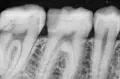

На каких зубах существует вероятность пульпита? 2. Есть ли вероятность, что на снимке присутствуют зубы, такие, что зуб значительно разрушен (от четырёх поверхностей), поэтому здесь требуется восстановление. То есть речь идёт о ситуации кариеса, когда пострадало более трёх поверхностей. Как известно, любой зуб имеет пять поверхностей (1. С внешней стороны. 2. С внутренней стороны (со стороны языка). 3. Со стороны левого соседнего зуба. 4. Со стороны правого соседнего зуба. 5. С жевательной стороны. Я понимаю, что точно диагноз нельзя поставить только по снимку, потому что нужен и визуальный осмотр, но речь идёт просто о возможности (подозрительных зубах и наиболее сложных).

Прям четких пульпитных явлений на снимке я не увидел. Шестой зуб сверху (26), требует установки коронки из-за большого количества пломбы, что по показаниям требуется реставрация вкладкой и коронкой. Не знаю про какой зуб идёт речь, но при разрушении коронковой части зуба более, чем на 50%, необходимо устанавливать коронки. Для более подробной консультации, обратитесь к стоматологу на очный приём.